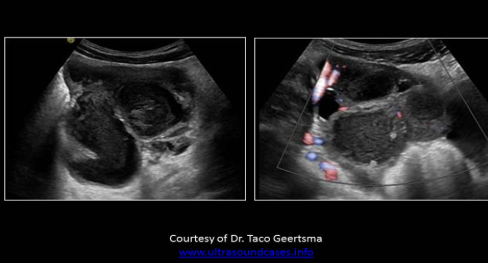

Pyosalpinx (PID)

Tubo-ovarian abscess USA

Abnormally thickened endometrium

Hydrosalpinx/pyosalpinx

Complex adnexal mass

Adnexal borders

Septations and debris

Gassy (DIRTY) SHADOWING may be seen